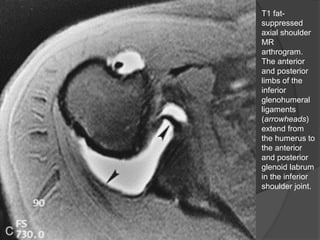

T1 fat-

suppressed

axial shoulder

MR

arthrogram.

The anterior

and posterior

limbs of the

inferior

glenohumeral

ligaments

(arrowheads)

extend from

the humerus to

glenoid labrum

in the inferior

shoulder joint.

• 56.

T1 fat- suppressed axial shoulder MR arthrogram. Theanterior and posterior limbs of the inferior glenohumeral ligaments (arrowheads) extend from the humerus to the anterior and posterior glenoid labrum in the inferior shoulder joint. Dr. Emanuel R. Dantas